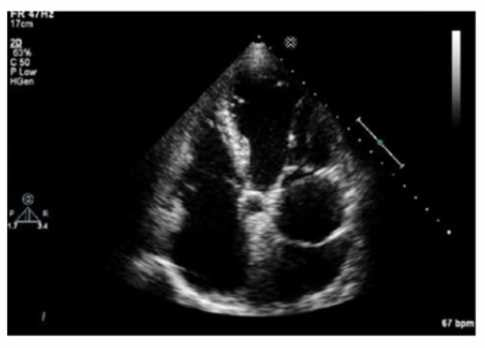

Which finding is shown in this image?

Answer(s): A

Explanation:

The echocardiographic image shows a mobile, highly echogenic, mesh-like structure within the right atrium consistent with the Chiari network. The Chiari network is an embryologic remnant of the right valve of the sinus venosus, appearing as a fenestrated, reticulated membrane that is usually thin and mobile, found near the orifice of the inferior vena cava or the coronary sinus.

This structure is benign and often an incidental finding but can be confused with thrombus or atrial tumors. Unlike left atrial thrombus, which appears as a more solid, immobile mass often located in the left atrial appendage, the Chiari network is mobile and located in the right atrium. Cor triatriatum is a rare congenital membrane dividing the left atrium into two chambers and appears differently on echocardiography. Artifact refers to non-anatomic echoes which do not persist or move consistently.

Recognition of Chiari network is important to avoid misdiagnosis, and its characteristics are well described in echocardiography literature such as the "Textbook of Clinical Echocardiography" and ASE